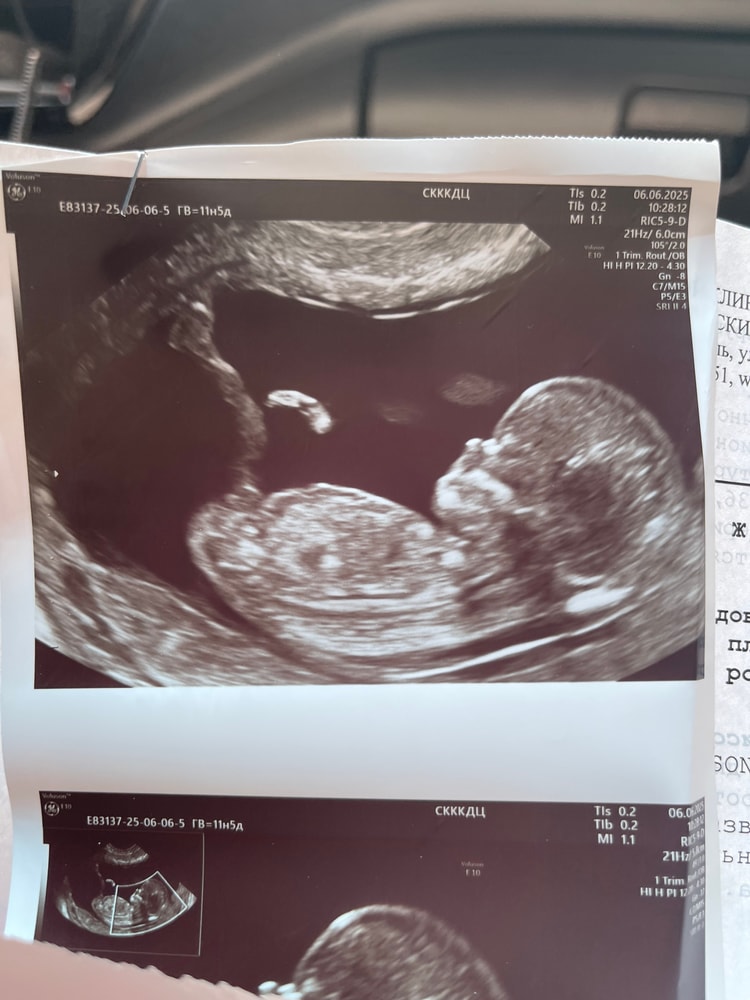

Видно ли тут пол?

Результаты УЗИВидно пол? Торчулька есть у всех,так я понимаю,а вот по направлению ее можно заподозрить пол. Но мне кажется тут кроме пуповины ничего не видно

Ну если это половой бугорок, я бы сказала девочка) но девочка еще может стать мальчиком😃 точно в 16 нелель уже видно

Victoria, и хорошо,что не видно,я так и хотела,не спалить в случае чего)) просто начали мне все говорить,что это парень как будто) а по мне,если это половой бугорок,то направление девочки😁решено погадать)пол пойду узнавать ближе к 16 Нед тоже.